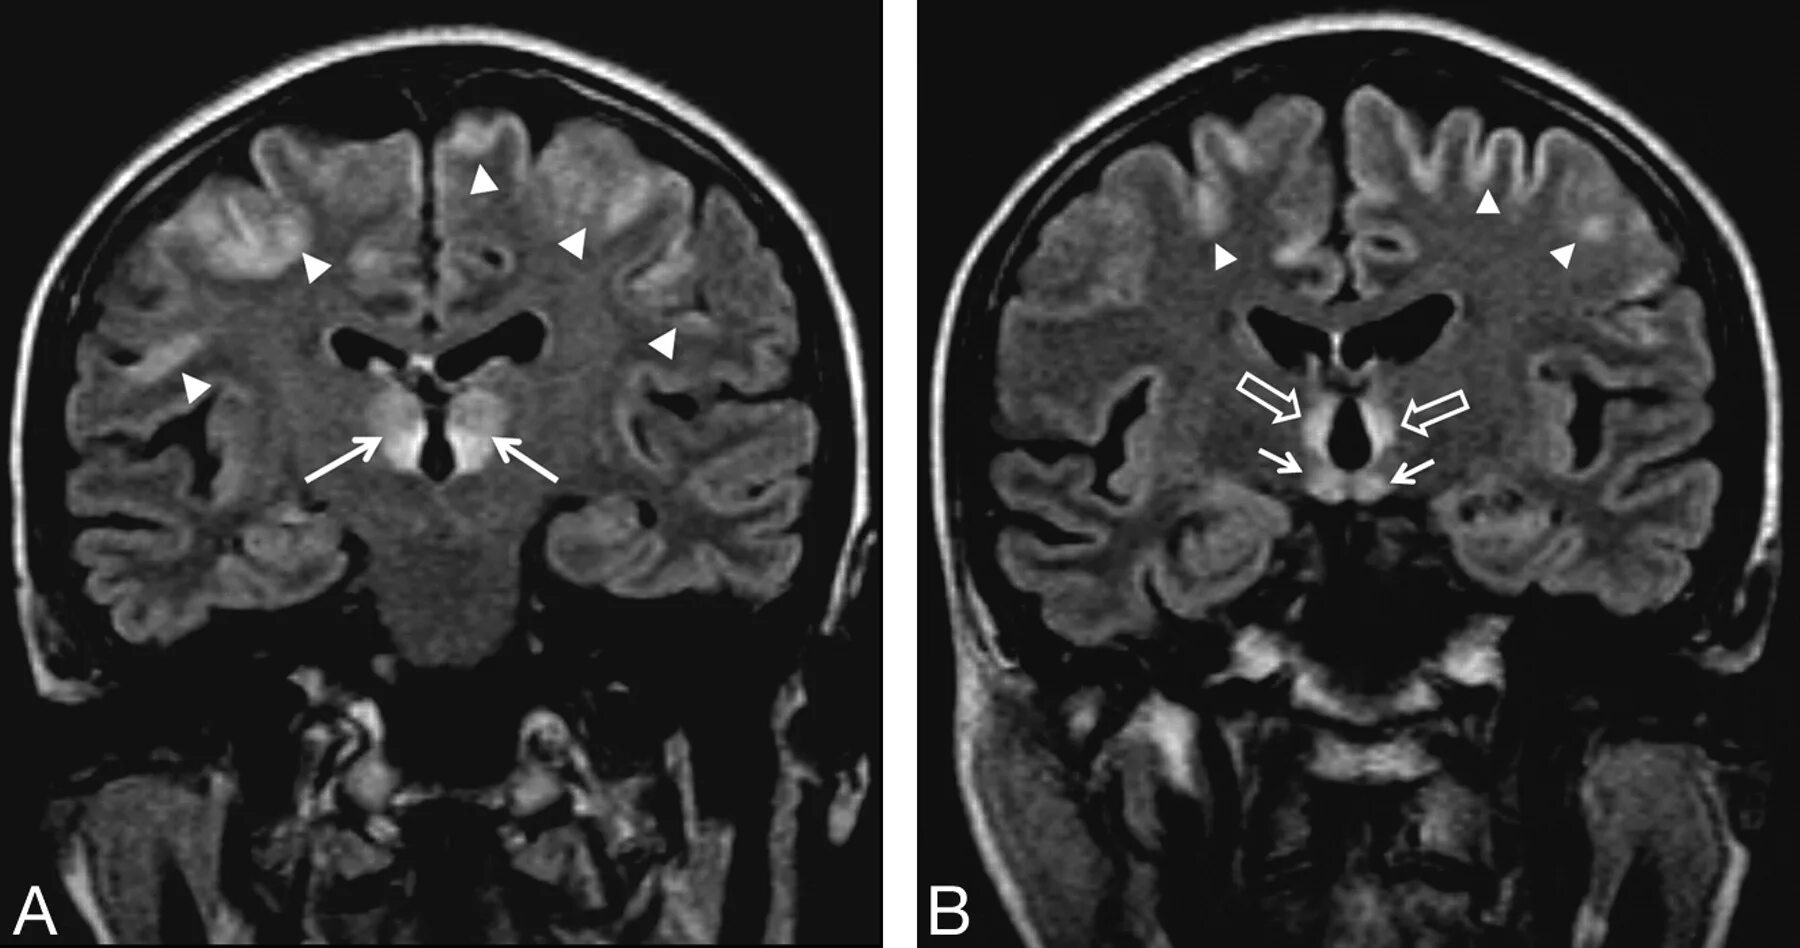

Гая вернике